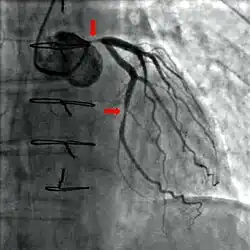

Coronary angiography of a critical sub-occlusion of the common trunk of the left coronary artery and the circumflex artery. (See arrows)

During coronary catheterization (often referred to as a "cath" or "cardiac cath" by physicians), blood pressures are recorded and fluoroscopy (X-ray motion picture) shadow-grams of the blood inside the coronary arteries are recorded. In order to create the X-ray pictures, a physician guides a small tube-like device called a catheter, typically ~2.0 mm (6-French) in diameter, through the large arteries of the body until the tip is just within the opening of one of the coronary arteries. By design, the catheter is smaller than the lumen of the artery it is placed in; internal (intra-arterial) blood pressures are monitored through the catheter to verify that the catheter does not block blood flow (as indicated by "dampening" of the blood pressure).